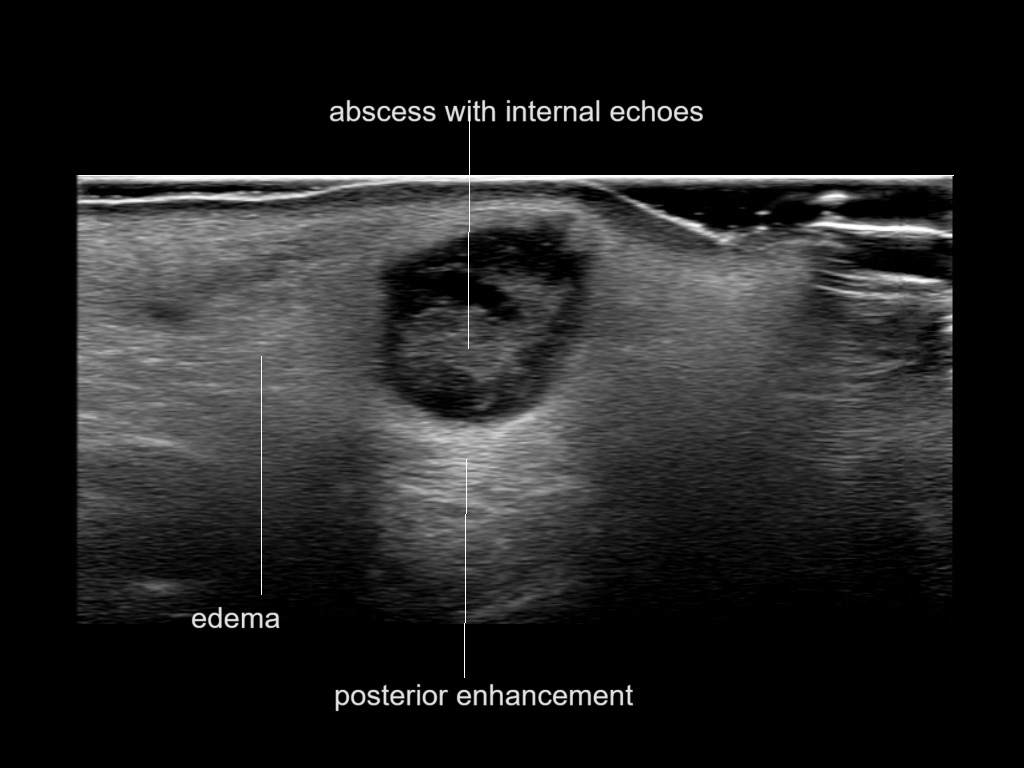

With ultrasound signs of inflammation can be visualized. Edema can be seen as a hyperechoic appearance of the subcutaneous fat, sometimes separated by hypoechoic fluid filled area’s, known as cobblestone appearance. Increased vascularization (hypervascularity) can be seen on colour Doppler. An abscess will appear as a fluid collection appearing as an irregular hypoechoic area with heterogeneous internal echoes and a thickened wall. Posterior acoustic enhancement can be present, and there is vascularity around but not within the mass. Under ultrasound guidance, abscesses can be managed by needle aspirations (18G) under antibiotic cover.

Study the first image to recognize the different layers. If you are sure about the layers, swipe to the second image to view the answer (if applicable).